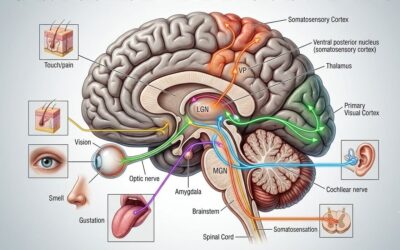

Obesity is no longer viewed as a simple imbalance between caloric intake and expenditure. It is a chronic metabolic condition influenced by endocrine signaling, inflammatory pathways, insulin resistance, and gut-host interactions. Within this framework, the microbiome functions less as a secondary contributor and more as a dynamic metabolic organ. Its composition affects energy harvest efficiency, short-chain fatty acid production, bile acid metabolism, systemic inflammation, and satiety regulation.

The rapid adoption of GLP-1–based therapies has reshaped patient expectations. These agents have demonstrated meaningful effects on appetite regulation, gastric emptying, and glycemic control. Emerging data suggest that GLP-1 therapies may also influence gut microbial composition, and that baseline microbial diversity may, in turn, affect therapeutic response. If confirmed in larger prospective studies, this bidirectional interaction could support more personalized metabolic protocols.

Modern obesity care must move beyond focusing solely on kilograms lost. Metabolic quality matters. Insulin sensitivity, inflammatory burden, hepatic function, body composition, and hormonal balance are central to long-term cardiometabolic health. The microbiome intersects with each of these domains. Short-chain fatty acids produced by gut bacteria participate in immune regulation and insulin signaling, while dysbiosis has been associated with adipose tissue inflammation and non-alcoholic fatty liver disease.